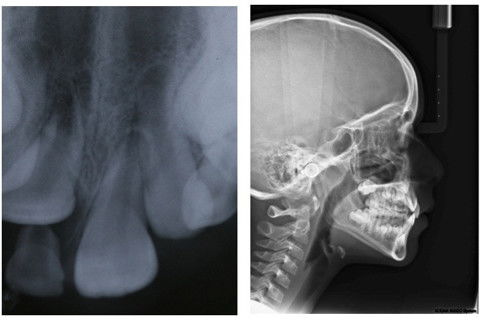

Foi solicitada radiografias e telerradiografia para observar quantidade de rizólise e rizogênese das dentições. Na radiografia periapical suspeitou-se de dilaceração coronoradicular do 11, porém, na telerradiografia a suspeita não foi confirmada.

Foi realizada a exodontia do dente 51. Observa-se o dente 11 irrompendo por palatina, necessitando de tratamento ortodôntico.